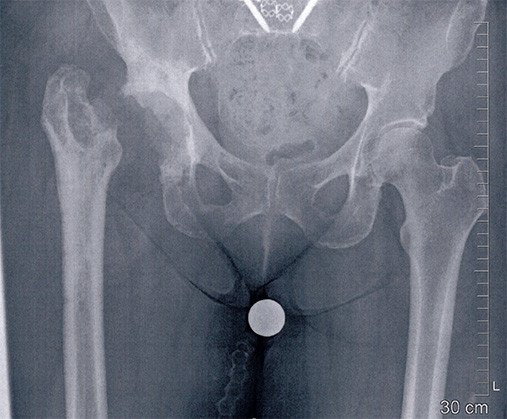

Seit einem Jahr hatte die Patientin erneut Hüftschmerzen. Die Abklärungen ergaben den Verdacht auf eine erneute Lockerung der Pfanne und allenfalls auch Schaftlockerung. Deshalb wurde sie erneut operiert. Intraoperativ zeigten sich klare Hinweise auf eine Infektion mit trübem Erguss. Die Hüfttotalprothese wurde daher komplett ausgebaut und die festsitzende Pfanne musste aus dem Becken herausgeschnitten werden. Der festsitzende Schaft konnte entfernt werden, nachdem der Oberschenkelknochen längs geschlitzt und aufgespreizt wurde.

Diese Situation wurde dann für 8 Wochen so belassen. Während dieser Zeit erhielt die Patientin für 6 Wochen eine antibiotische Behandlung. Nach 8 Wochen wurde die Hüfte erneut eingesetzt. Verwendet wurde wieder ein zementfreier Schaft und pfannenseitig eine Stützschale, die eine luxationssichere Pfanne aufnimmt. Die Patientin ist infektfrei und mit dem Verlauf nun zufrieden.